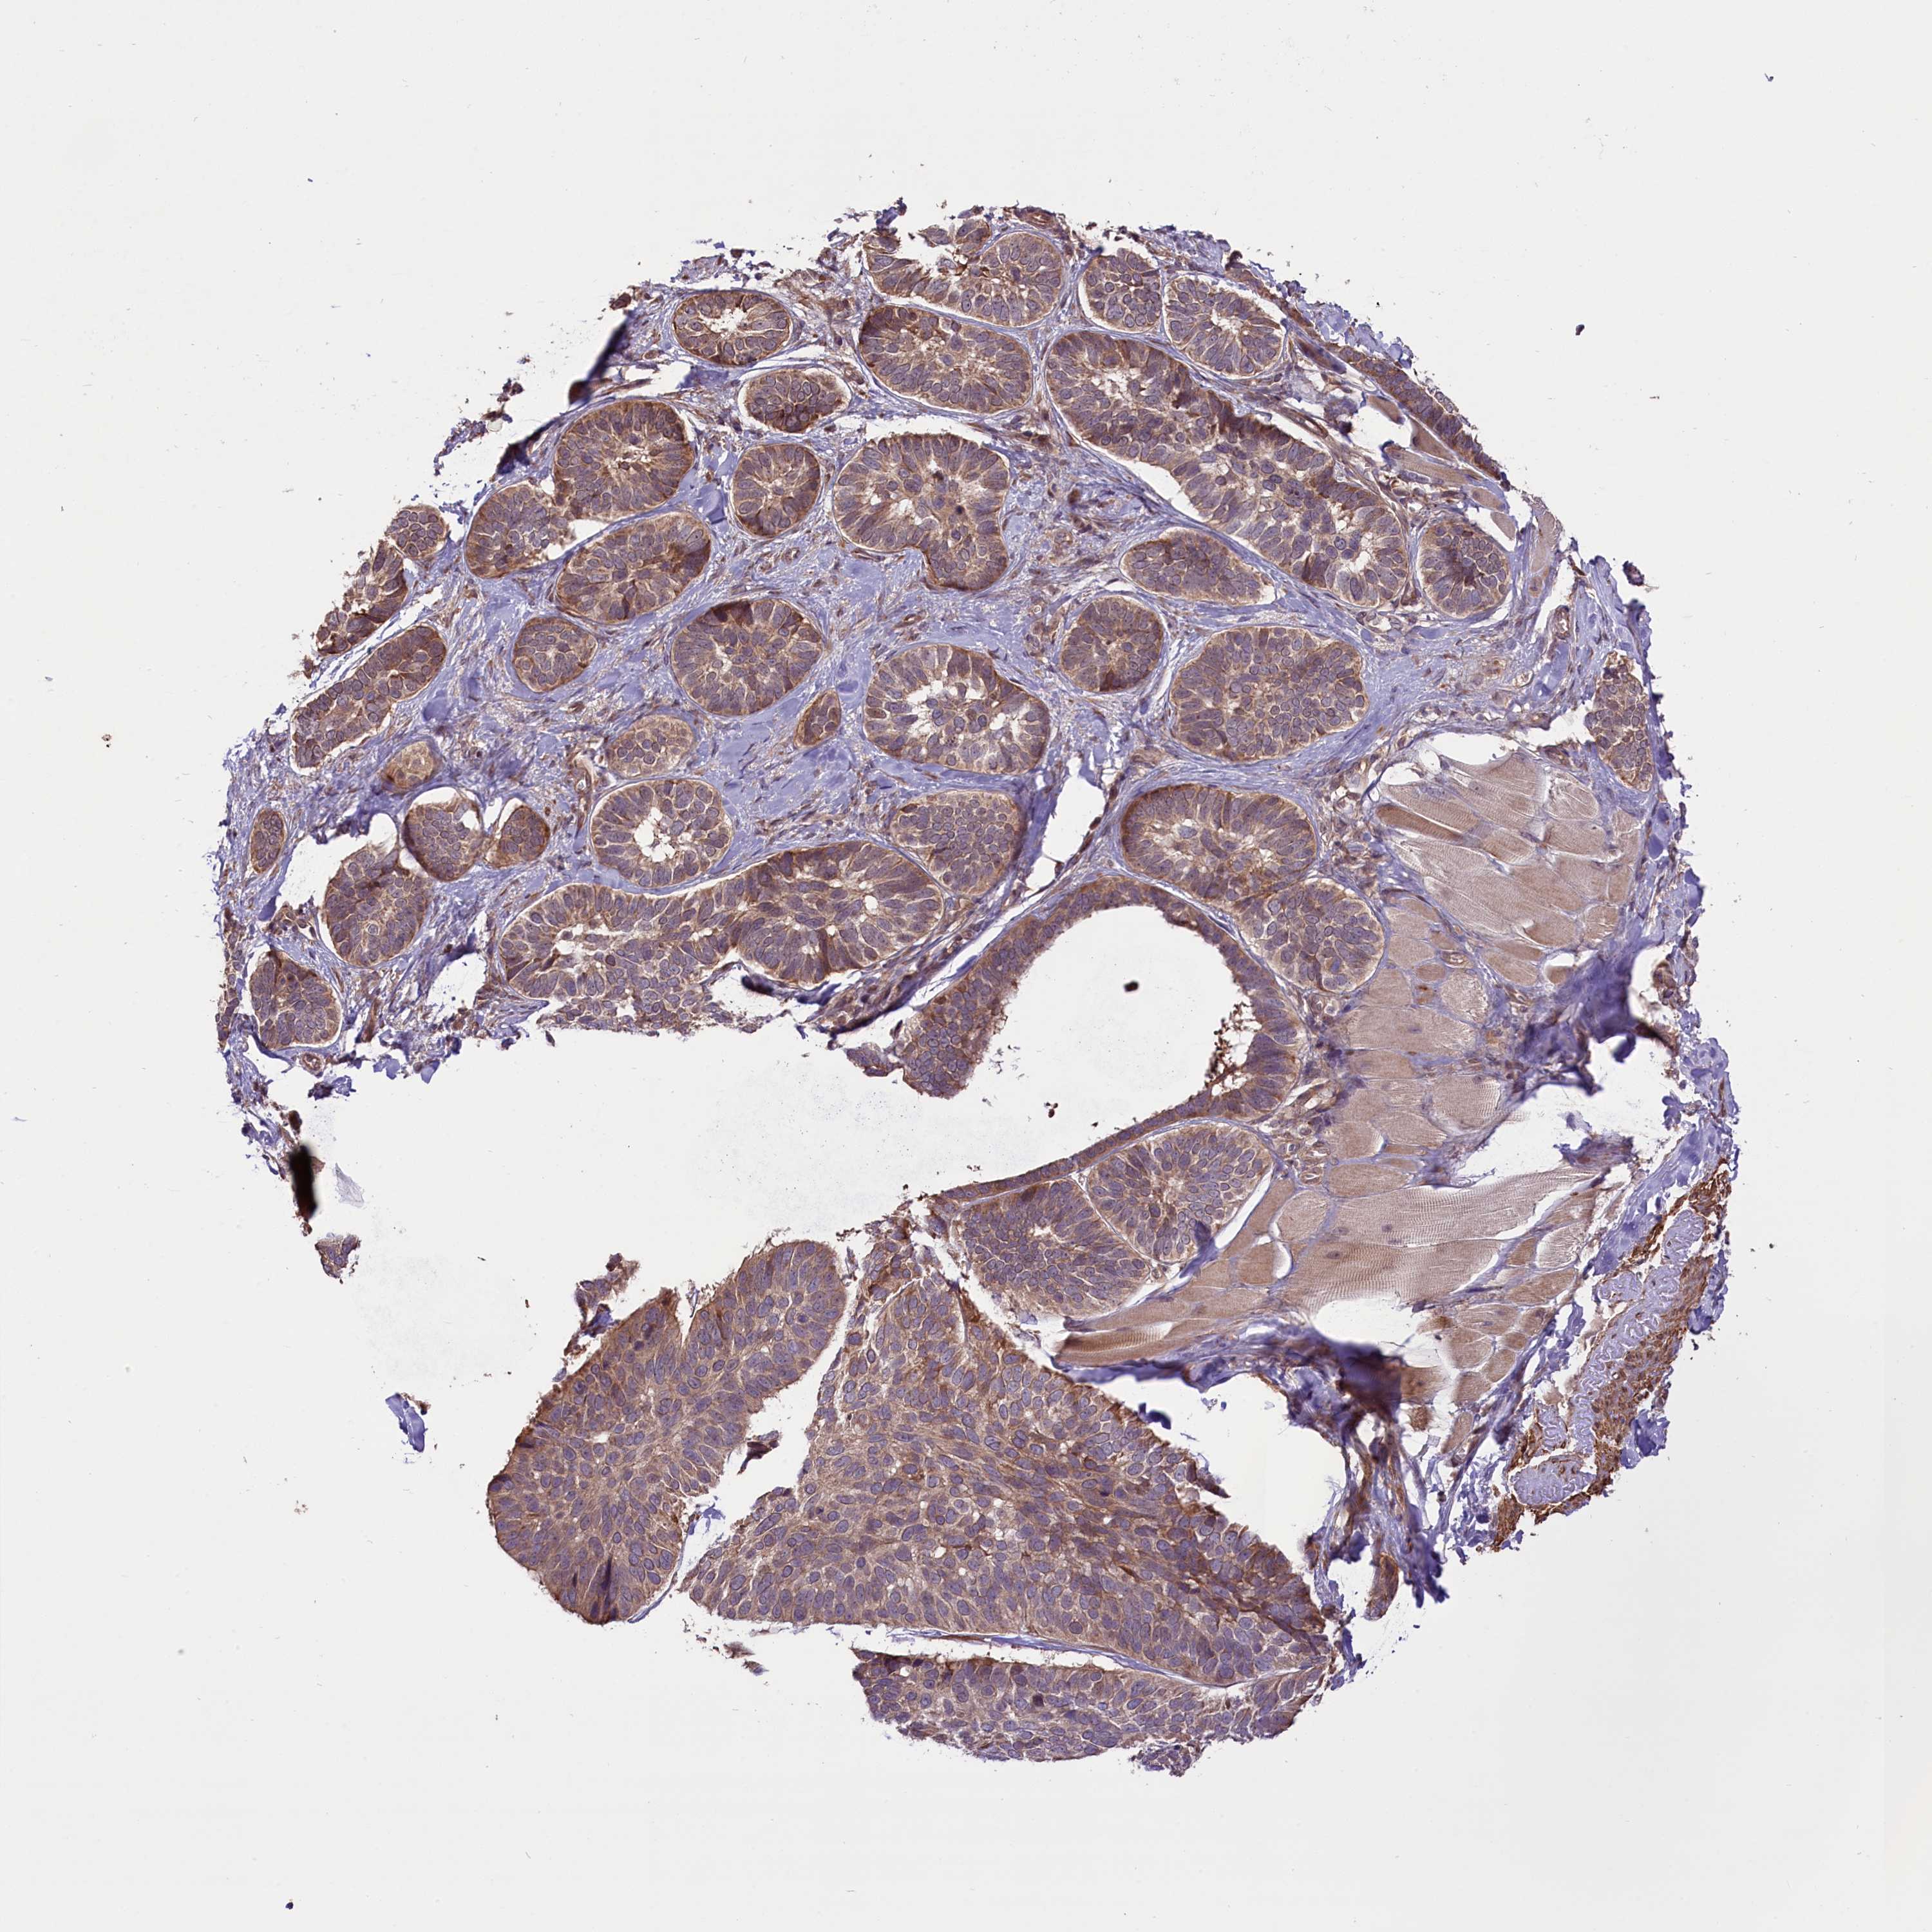

SKIN CANCER - Protein expressioni

A mouse-over function shows sample information and annotation data. Click on an image to view it in a full screen mode. Samples can be filtered based on level of antibody staining by selecting one or several of the following categories: high, medium, low and not detected. The assay and annotation is described here.

Antibody stainingi

Antibody staining in the annotated cell types in the current human tissue is reported as not detected, low, medium, or high, based on conventional immunohistochemistry profiling in selected tissues. This score is based on the combination of the staining intensity and fraction of stained cells.

Each image is clickable and will lead to virtual microscopy that enables deeper exploration of all samples and also displays staining intensity scores, fraction scores and subcellular localization as well as patient and tissue information for each sample.

Antibody CAB019400

Squamous cell carcinoma, metastatic, NOS